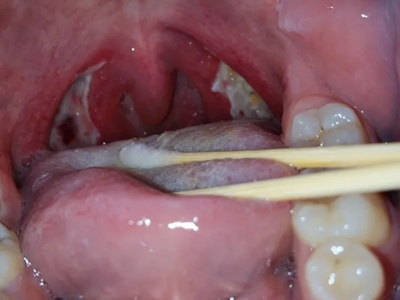

化脓性扁桃体炎扁桃体出现乳白色疙瘩图

化脓性扁桃体炎咽部两侧扁桃体增生肿大,呈肉疙瘩状,形状不规则,大小不等,黏膜表面凹凸不平,部分黏膜附有黄白色物质,伴有咽痛,吞咽时更加明显。